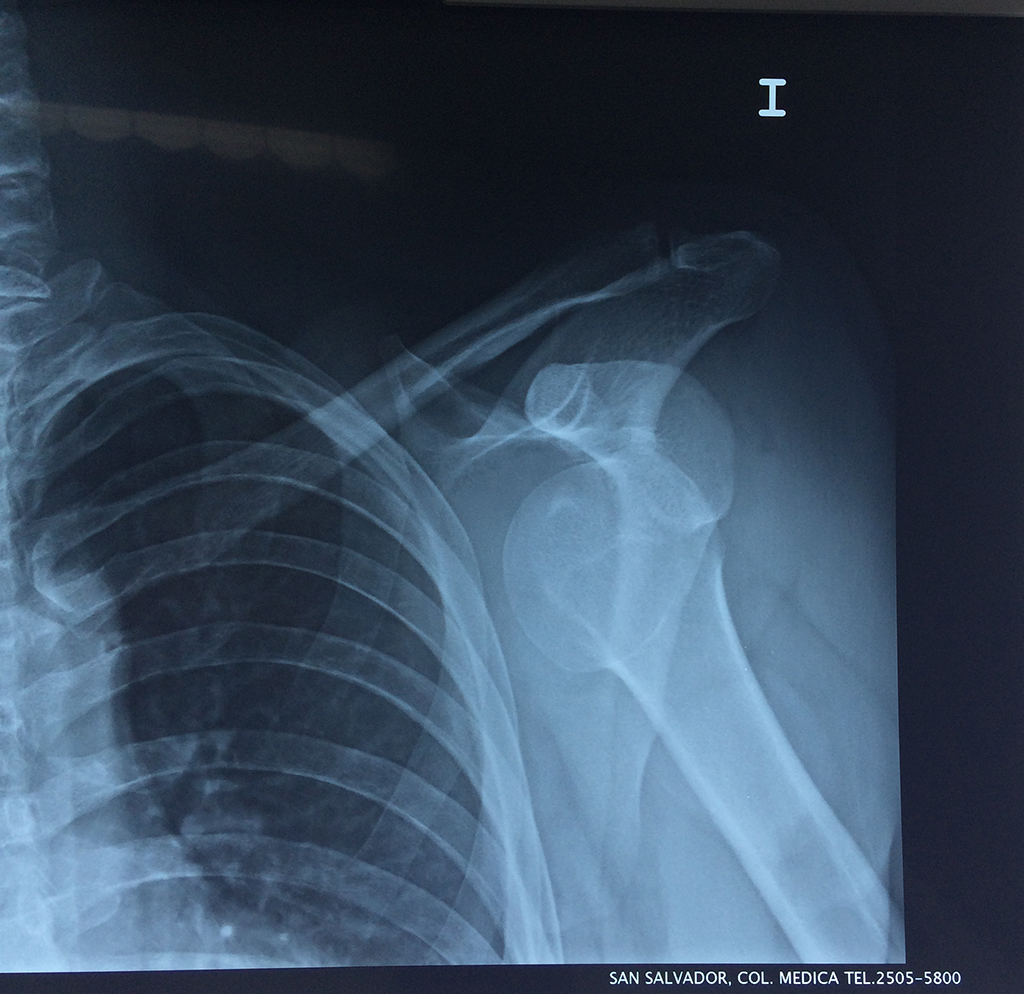

En anatomía humana, el hombro es la parte del cuerpo donde se une el brazo con el tronco. Está formado por la conjunción de los extremos de tres huesos: la clavícula, la escápula y el húmero; así como por músculos, ligamentos y tendones.

Exteriormente una envoltura de tejido blando circunda el conjunto, es la llamada cápsula articular que está reforzada por varios ligamentos que le dan estabilidad e impiden que los huesos se desplacen más allá de sus límites fisiológicos. Un conjunto de músculos y sus tendones se unen a las superficies de los huesos y hacen posible la movilidad de la articulación, entre ellos es muy importante el manguito rotador formado por cuatro músculos que proporcionan movilidad y estabilidad al hombro.